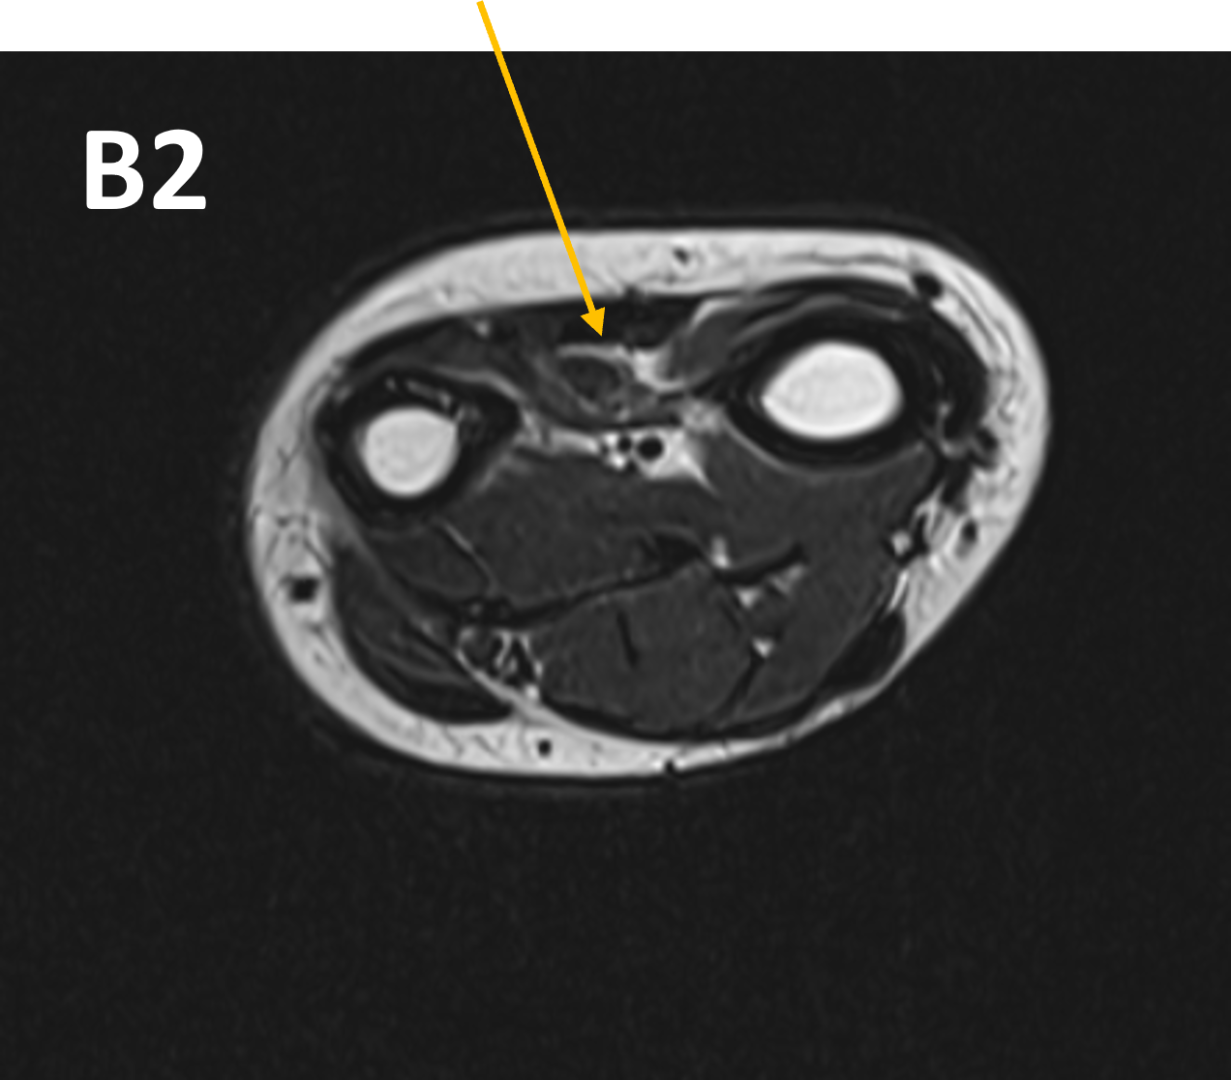

- B 2 : Volume loss with fatty atrophy of brachioradialis, supinator, extensor carpi radialis longus and brevis muscles ,due to chronic denervation changes.